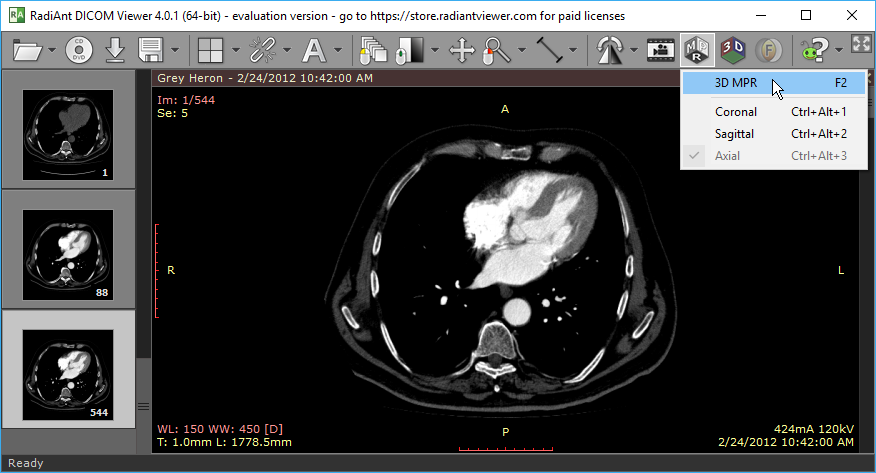

打开 3D MPR 窗口

1. 在 2D 查看器窗口中打开体积序列,点击工具栏上的 MPR 按钮,然后选择 3D MPR。也可使用 F2 快捷键。